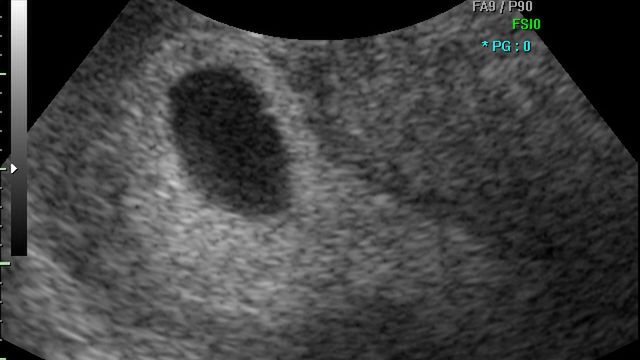

/ 3Płód w 9 tygodniu ciąży (bliźniaki jednokosmówkowe) - rozwój dziecka

Formują się oczy i ząbki dziecka